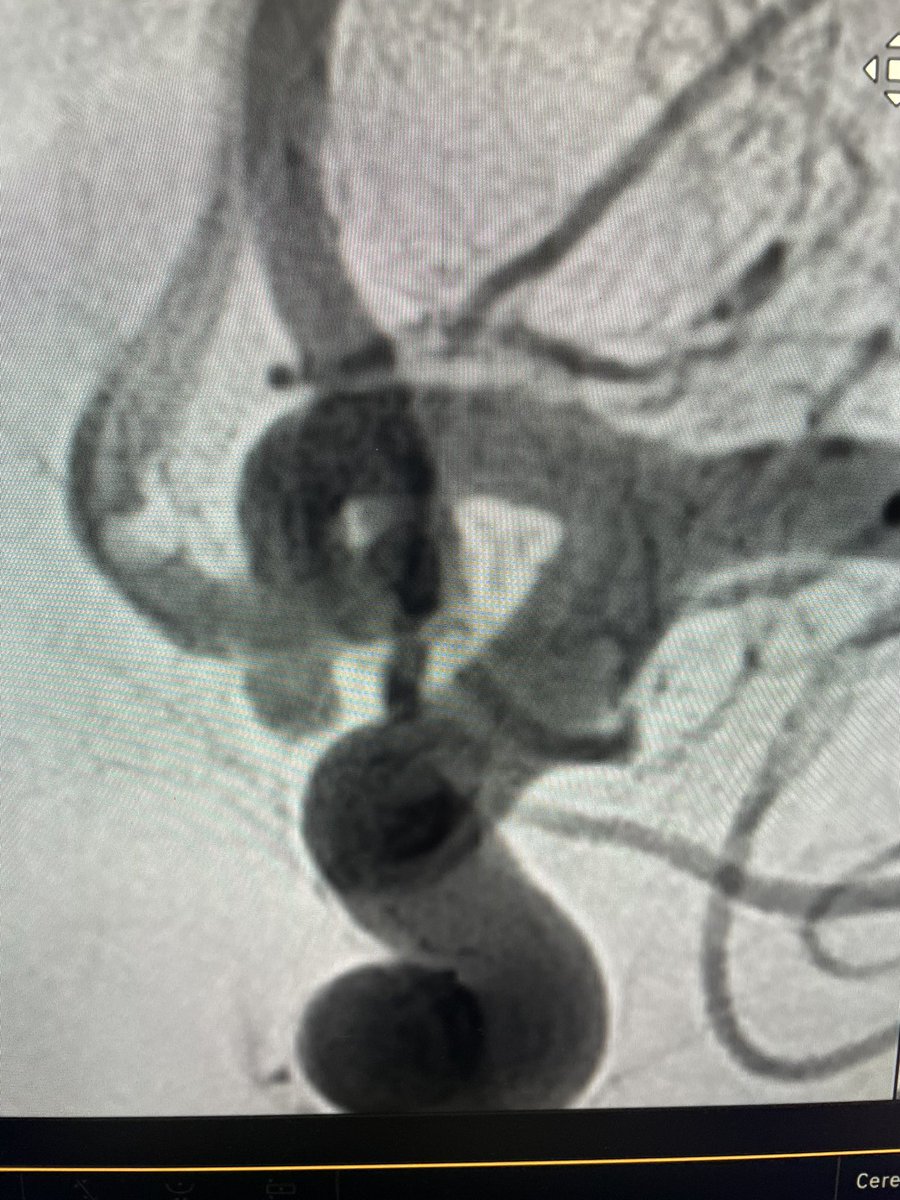

El Dr. Carlos Pérez@Justcharly9, nos resume en menos de 15 minutos los dos principales ensayos clínicos que comparan tratamiento Endovascular VS Quirúrgico (ISAT, IBRAT) de aneurismas rotos.